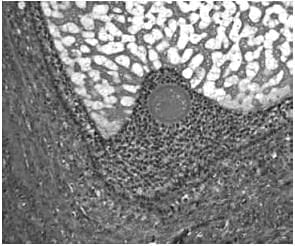

The development of a follicle, from

(a) The primordial follicle is surrounded by a single layer of undifferentiated epithelial cells and is insensitive to gonadotropins

(b) The early antral follicle has well-differentiated theca (immunostained brown) and granulosa cell layers surrounding the developing antral cavity with the oocyte ( Small antral)

(c) The pre-ovular follicle with the oocyte surrounded by the cumulus oophorus with well-differentiated granulosa and theca cell layers (Preovulatory stages)